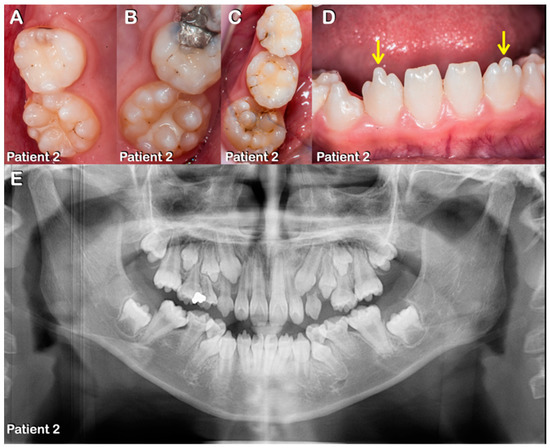

Figure 2.

Patient 2. (A–E) Mixed dentition. (A–C) Round-shaped primary and permanent molars with multiple supernumerary cusps. (D) Prominent medial mamelon of the mandibular lateral permanent incisors (arrows). (E) Panoramic radiograph showing agenesis of all third permanent molars, single-rooted primary and permanent molars, and taurodontism.